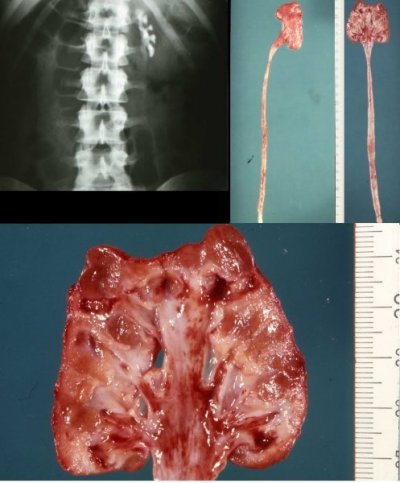

Als Beispiel die kleine stumme Niere bei einem Mädchen. Anhand des Nephrektomiepräparates war die Differentialdiagnose pyelonephritische Schrumpfniere oder Hypoplasie bzw. eine Kombination nicht mehr möglich (Abbildung 22).

Auch bei dieser kleinen Niere war anhand der Histologie die Ursache der pathologischen Veränderungen nicht mehr eindeutig zu klären. Makroskopisch gewann man den Eindruck einer pyelonephritischen Schrumpfniere (narbige, leicht bucklige Oberfläche, vermehrtes Hilusfestgewebe, veringerung des Parenchyms und narbig verändertes Nierenbecken). Die histologische Untersuchung der "kleinen Niere" ergab jedoch eine interstitielle Nephritis, ohne Anhalt für Pyelonephritis (Abbildung 23).